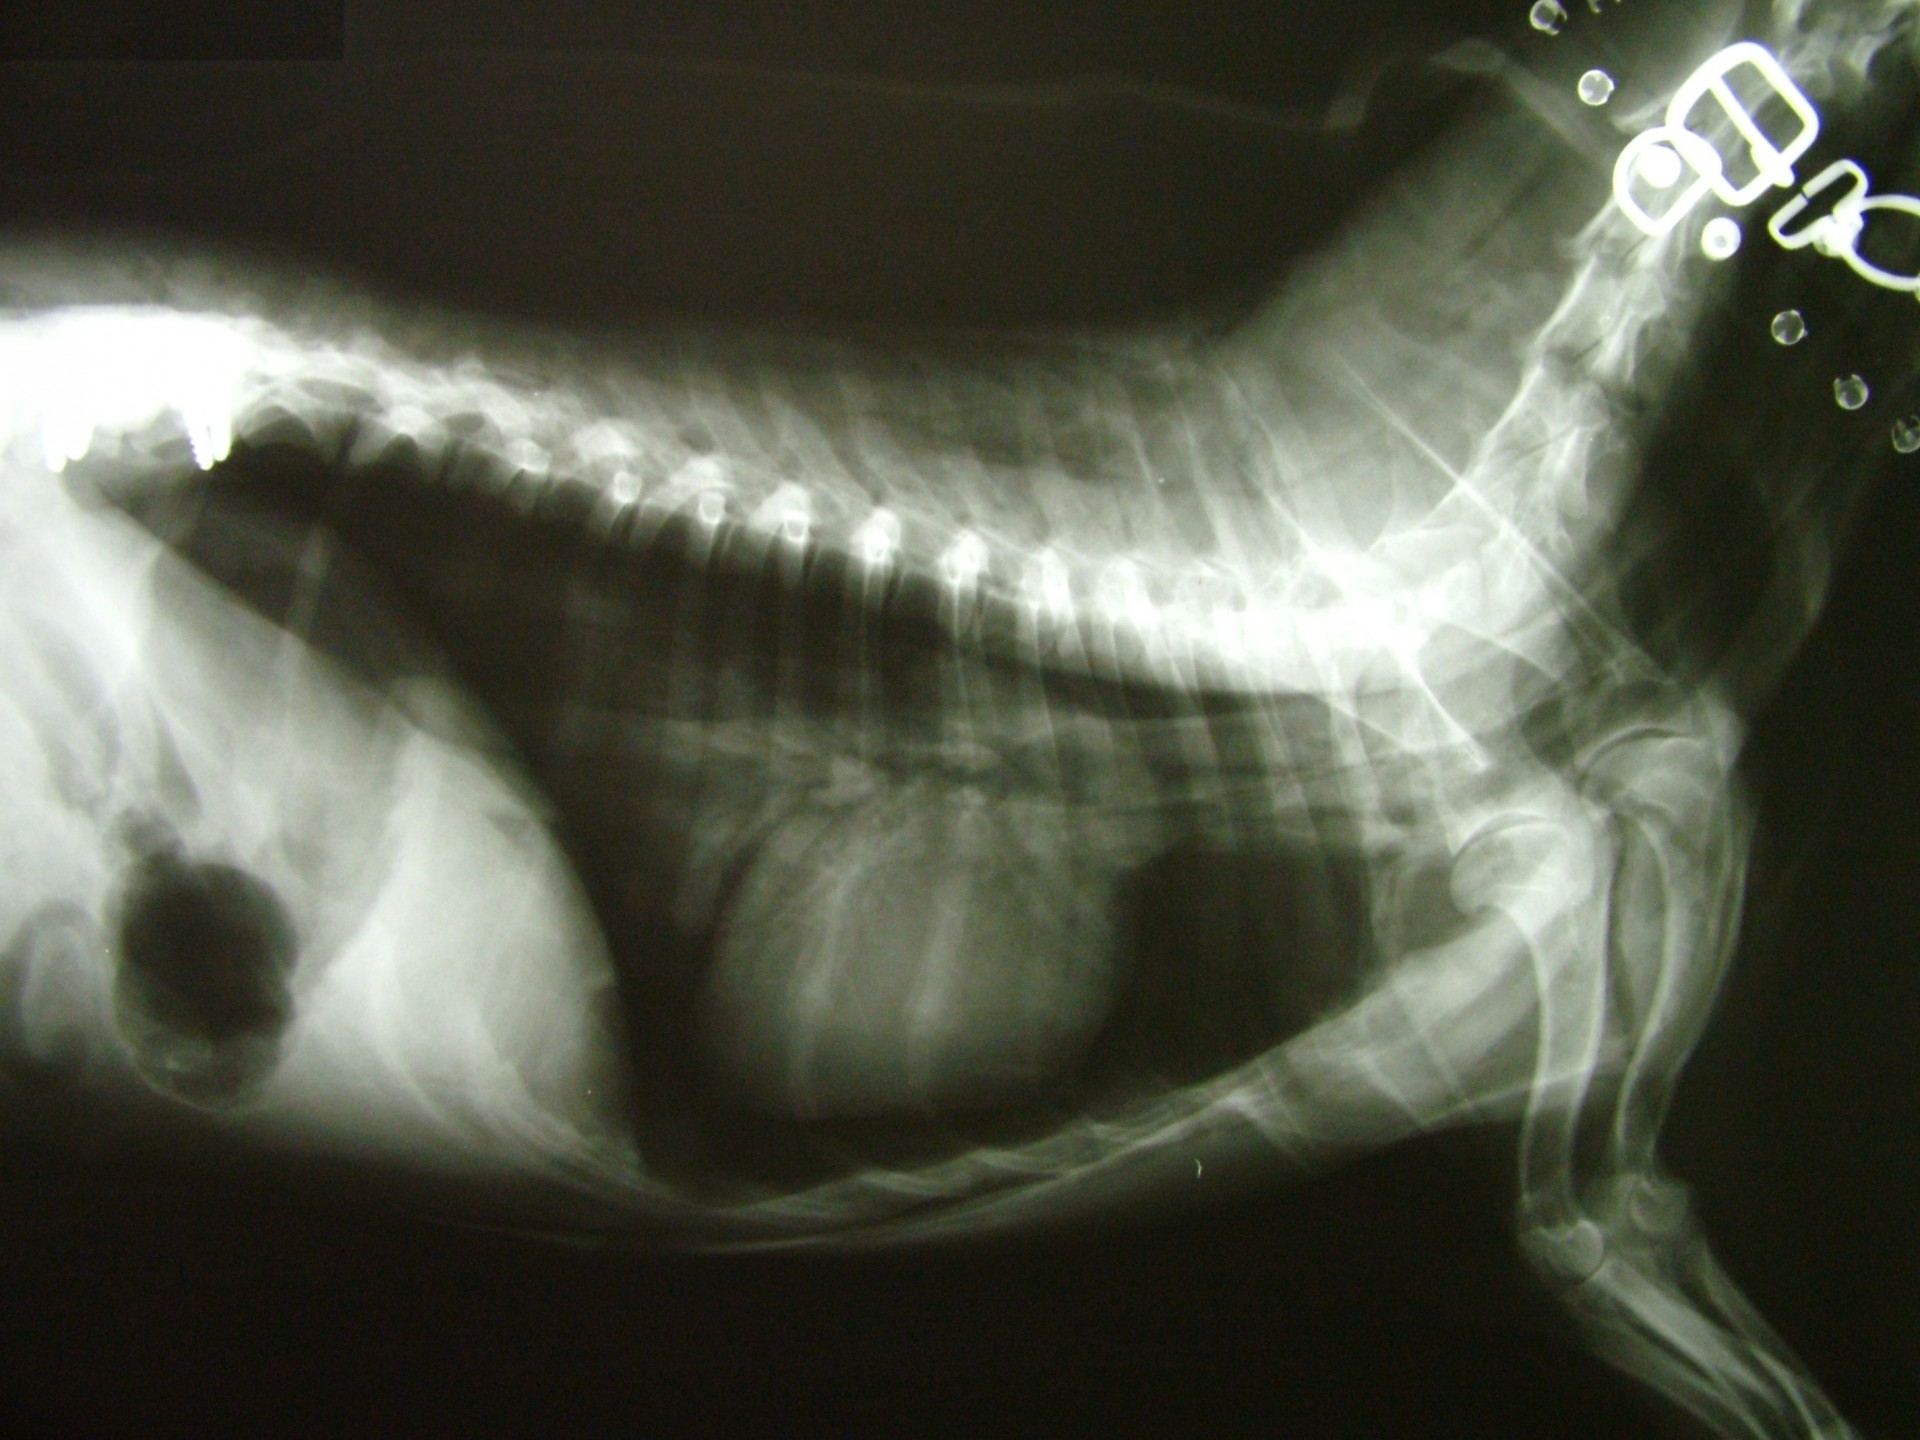

A gerinctörések kialakulását minden esetben valamilyen súlyos trauma előzi meg. Az esetek döntő részében a tulajdonos a kórelőzményben ezt elmondja, de nem egy esetben találkoztunk talált, ismeretlen kórelőzményű, súlyos neurológiai tüneteket mutató állattal.A trauma általában kutyák esetében gázolás, kistestű kutyák (yorkshire terrier, chihuahua) esetében nagytestű kutya harapása, macskák esetében kutyaharapás, gázolás vagy emeletről történő leesés.

A gerinctörött állatok általában súlyos fokú hátsó testfél gyengeség tüneteit mutatják, a sérülés helyétől függően (a gerincoszlop mely szakaszán alakult ki gerincvelő sérülés) azonban a tünetek a mellső végtagokat is érinthetik. Ilyen tünetegyüttes a Schiff-Sherrington syndroma, melyben a gerincvelő sérülése mögötti területen petyhüdt bénulás, míg a sérülés előtti területen a nyújtó izmok fokozott tónusának megjelenése jellemző.

A gerincsérült állatokat ért traumás behatás természetesen nemcsak a gerincoszlopot, hanem egyéb szerveket is érhetik, ezért a gerincvelő sérülés ellátásához rendelkezésünkre álló idő (általában 24 óra) sok esetben az egyéb szervi sérülések miatt meglehetősen rövid vagy az egyéb sérülések következményei - egy akár sikeres gerincműtétet követően is - az állat halálát okozhatják. Ezért a balesetes állatok sérüléseinek ellátása fontossági sorrendben kell hogy megtörténjen, hisz eredményt csak akkor érhetünk el, ha az állat állapotát stabilizáljuk.